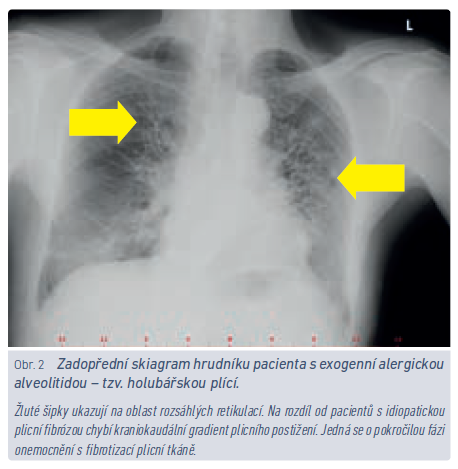

S problematikou EAA by měli být obeznámeni nepochybně lékaři, kteří poskytují pracovnělékařské služby. Vyvine‑li nemocný v riziku kontaktu s inhalačními antigeny dechové obtíže, zejména pokud existuje časová a místní souvislost mezi vznikem obtíží a expozicí, je namístě uvažovat o EAA (obr. 2). Nemocný by měl být odeslán k plicnímu vyšetření, a je‑li diagnóza potvrzena, znamená to obvykle nutnost přeřazení z rizikového provozu. Inhalačních antigenů, které byly popsány v souvislosti s rozvojem EAA, je několik stovek.11 Obecně největší riziko představuje opakovaný kontakt s plísněmi a bakteriemi (farmáři, pracovníci v zemědělství, chovatelé hospodářských zvířat, ale i vlhké stavby, bazény apod.) anebo s ptačím peřím (rizikem jsou ohroženi též chovatelé holubů a okrasného ptactva a riziko představují i péřové lůžkoviny). Zatímco zjišťovat preventivně povahu lůžkovin nemocného je spíše bizarní, představu o zaměstnání pacienta by praktický lékař mít měl. Občas se setkáváme v kolonce pracovní anamnéza s údajem osoba samostatně výdělečně činná. Tento údaj je z hlediska možných zdravotních rizik spojených s povoláním zcela nedostatečný a nevypovídá o tom, zda pacient vede někomu účetnictví, nebo chová hovězí dobytek.

U nefibrotických forem EAA se můžeme setkat s časovou vazbou mezi expozicí inhalačnímu antigenu a příznaky. Typickým vodítkem k diagnóze jsou opakované epizody dušnosti, kašle, subfebrilií, bolestí svalů a kloubů, které se rozvinou po kontaktu s inhalačním antigenem. U značné části pacientů ale tato souvztažnost chybí, a tak je třeba, aby měl lékař potenciální zdravotní rizika vyplývající z pacientova zaměstnání/koníčků na mysli a v případě rozvíjející se námahové dušnosti, dlouhodobějšího kašle nebo abnormálního poslechového nálezu nemocného aktivně odeslal k plicnímu vyšetření.12 Základem léčby EAA je zabránění dalšímu kontaktu s vyvolávajícím agens a opakování této mantry nemocným není nikdy dost.13